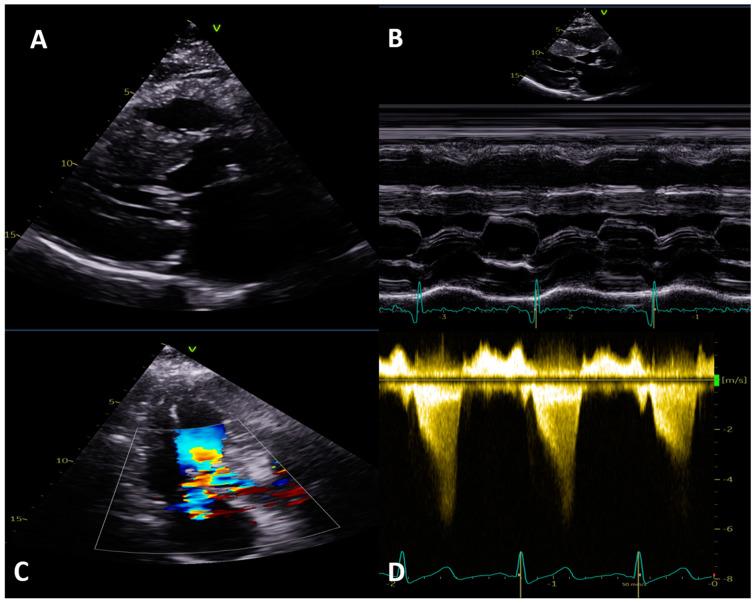

Hypertrophic cardiomyopathy (HCM) is characterized by abnormal growth of the myocardium with myofilament disarray and myocardial hyper-contractility, leading to left ventricular hypertrophy and fibrosis. Where culprit genes are identified, they typically relate to cardiomyocyte sarcomere structure and function. Multi-modality imaging plays a crucial role in the diagnosis, monitoring, and risk stratification of HCM, as well as in screening those at risk. Following the recent publication of the first European Society of Cardiology (ESC) cardiomyopathy guidelines, we build on previous reviews and explore the roles of electrocardiography, echocardiography, cardiac magnetic resonance (CMR), cardiac computed tomography (CT), and nuclear imaging. We examine each modality's strengths along with their limitations in turn, and discuss how they can be used in isolation, or in combination, to facilitate a personalized approach to patient care, as well as providing key information and robust safety and efficacy evidence within new areas of research.

肥厚型心肌病(HCM)的特征是心肌异常生长,伴有肌丝排列紊乱和心肌过度收缩,导致左心室肥厚和纤维化。在确定致病基因的情况下,它们通常与心肌细胞肌节的结构和功能有关。多模态成像在HCM的诊断、监测和风险分层以及筛查高危人群方面发挥着关键作用。继欧洲心脏病学会(ESC)首部心肌病指南近期发布之后,我们在以往综述的基础上,探讨心电图、超声心动图、心脏磁共振成像(CMR)、心脏计算机断层扫描(CT)和核成像的作用。我们依次审视每种模态的优势及其局限性,并讨论如何单独或联合使用它们,以促进个性化的患者护理方法,同时在新的研究领域提供关键信息以及有力的安全性和有效性证据。